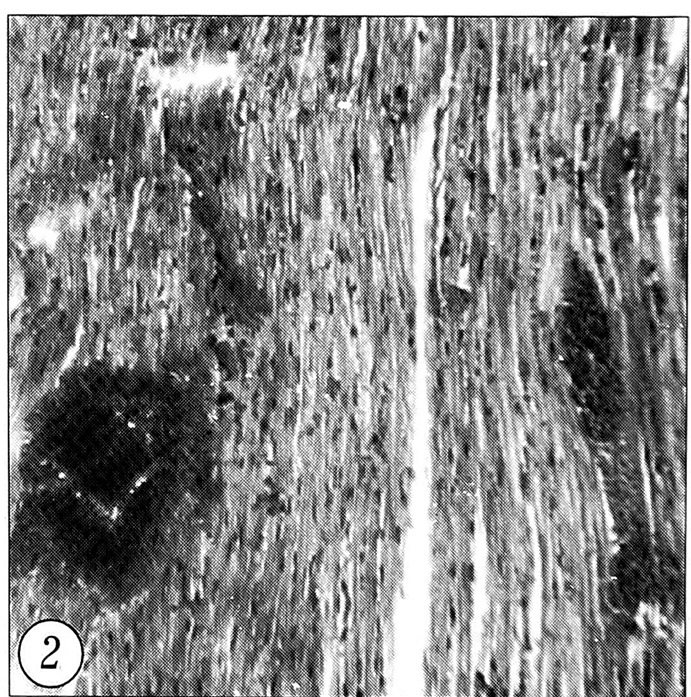

При анализе изменений миокарда у животных контрольной группы на первый план также выступали нарушения циркуляторного характера: полнокровие сосудов всех типов, необычные для миокарда мелкие субэпикардиальные кровоизлияния, гемолиз эритроцитов в полнокровных сосудах (рис. 2). Дистрофические изменения кардиомиоцитов проявлялись отсутствием на значительных участках поперечной исчерченности волокон и наличием зернистости цитоплазмы.

Рис. 2. Микроскопическая картина миокарда кролика контрольной группы: на фоне фрагментированных кардиомиоцитов с явлениями белковой дистрофии видны множественные кровоизлияния (окраска гематоксилином и эозином, ув. 140).